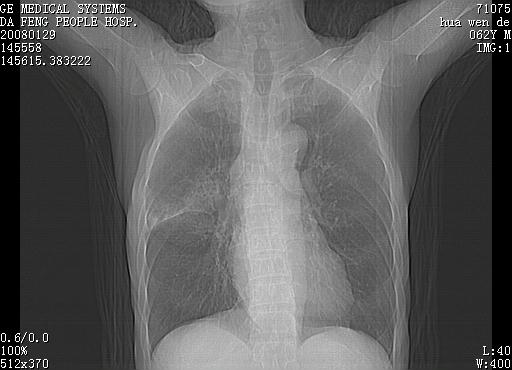

男性,67岁。作肺部检查时发现

右肺脓肿 胸腔胃

考虑1、右肺周围型肺癌可能性大。

2、贲门失迟缓症可能,建议钡餐检查。

考虑:胸腔胃并支气管瘘(并发肺炎,肺脓肿形成)。

理由:1、右上肺内病灶,空洞形成,有液平。

2、肺内多处炎症。

3、前段肺内炎症,支气管引流通畅,与肿块无关系。

1.整个食管扩张,未见明显占位性病变,贲门区亦未见明显占位病变,考虑:贲门失驰缓症;

2.右上肺病变边缘可见毛刺,囊壁厚度不均匀,周围境界较清楚,未见炎性渗出性影,右上肺外带可见片状影,边缘不清,考虑:肺癌伴空洞形成、右上肺炎。

食管全程扩张,壁均匀不厚,喷门失弛缓症

右上肺空洞可见液平,临近肺野磨玻璃密度,考虑1.结核2.脓肿